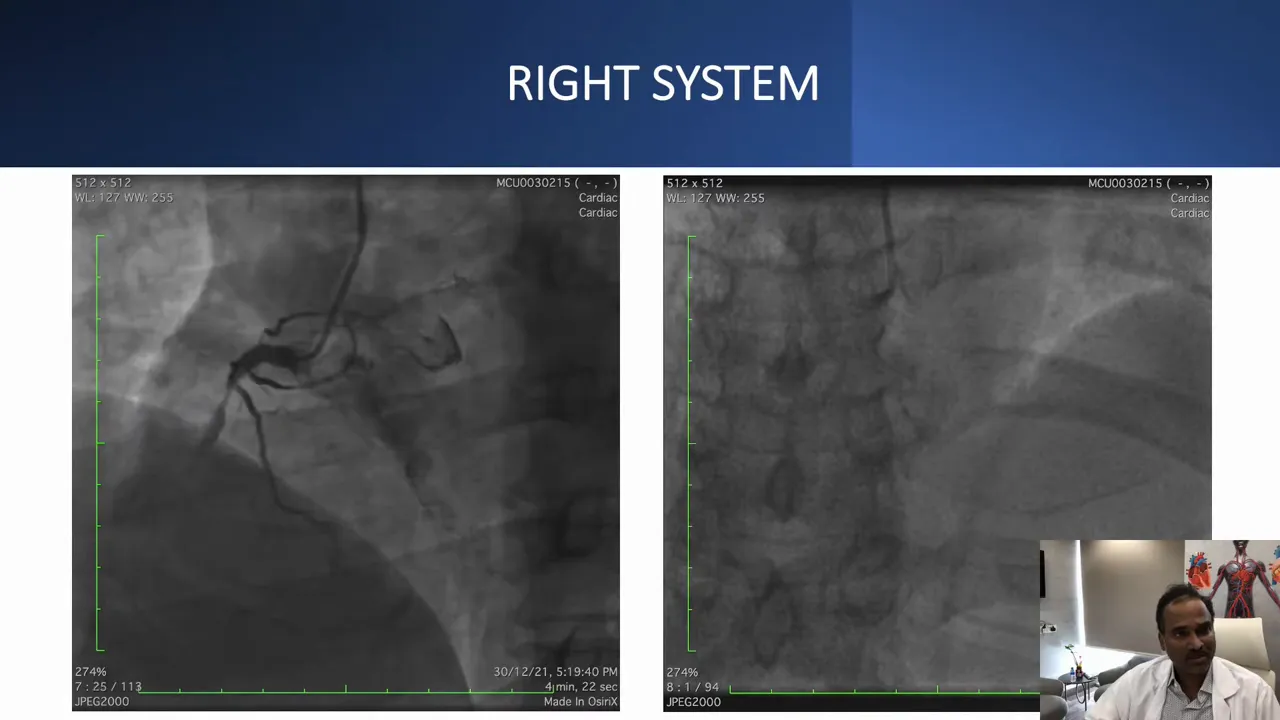

A 55-year-old man with type 2 diabetes and hypertension presented with Canadian Cardiovascular Society class III effort angina for one month and recent rest angina. He had a diagnosis consistent with non-ST elevation myocardial infarction and preserved left ventricular systolic function. Renal function was normal. The left coronary system had significant disease requiring PCI, and the right coronary artery (RCA) had a short CTO with an uncertain distal cap and favorable distal vessel quality.

This angiographic projection suggested a short RCA CTO. At first glance the lesion looked straightforward on one projection, but other angiographic angles revealed a more complex course.

After revascularizing the left system, the RCA CTO attempt began. Dual injection showed a short CTO and two proximal lesions that needed ballooning to avoid getting “stuck” between lesions during antegrade escalation. Lesion preparation with a 2.5 mm balloon opened these proximal stenoses and improved guidewire access to the cap.

Dual injections help by simultaneously visualizing both proximal and distal segments to understand the exact course of the vessel and the position of the distal cap.